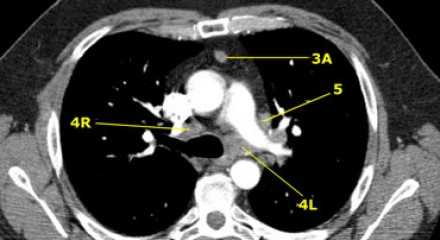

Лимфатические узлы 3 группы не примыкают к трахее в отличии от лимфатических узлов 2 группы. Они подразделюятся на: 3А кпереди от сосудов 3Р позади пищевода/превертебрально Они не доступны при медиастиноскопии. 3Р группа может быть доступна при чреспищеводной эхокардиографии.

На изображении слева 3А узел в преваскулярном пространстве. Обратите внимание так же на ниже расположенные паратрахеальные узлы справа относящиеся к 4R группе.

4R. Правые нижние паратрахеальные лимфатические узлы

- Верхняя граница: пересечение нижнего края левой плечеголовной вены с трахеей.

- Нижняя граница: нижний края непарной вены. 4R узлы распространяются до левого края трахеи.

На изображении слева мы видим 4R паратрахеальные узлы. Кроме того здесь представлен узел кнаружи от дуги аорты, то есть 6 группы.

4L. Левые нижние паратрахеальные лимфатические узлы

4L узлы расположенные слева от левой стенки трахеи, между горизонтальными линиями проведенными касательно верхней стенке дуги аорты и линией проходящей через левый главный бронх на уровне верхнего края верхнедолевого бронха. Они включают паратрахеальные узлы расположенные кнутри от артериальной связки.

Узлы 5 группы (аортопульмонального окна) расположены кнаружи от артериальной связки.

На левом изображении над уровнем легочного ствола представлены нижние паратрахеальные узлы слева и справа, так же здесь представлены узлы 3 и 5 групп.

Изображение слева выше уровня карины. Слева от трахеи 4L узлы. Обратите внимание что они расположены между легочным стволом и аортой, но не в аортопульмональном окне, потому что они лежат медиальнее артериальной связки. Лимфатические узлы латеральнее легочного ствола относятся к 5 группе.

- 5. Субаортальные лимфатические узлы

- Субаортальное или аортопульмональное окно расположено кнаружи от артериальной связки и проксимальнее первой ветви левой легочной артерии и лежит в пределах медиастинальной плевры.

- Парааортальные лимфатические узлы лежат кпереди и кнаружи от восходящего отдела аорты и между верхним и нижним краями дуги аорты.